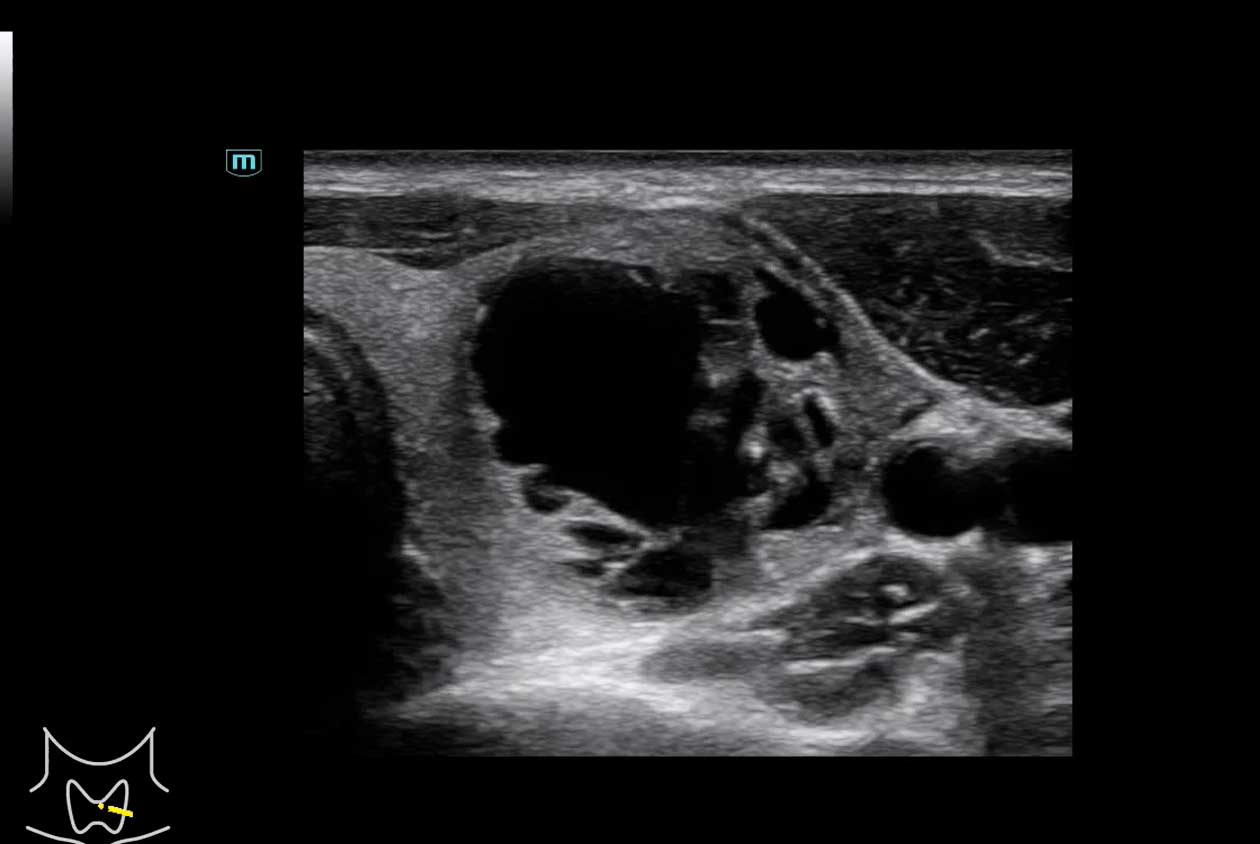

Women's Health | Radiology | Cardiovascular Imaging

Advanced Technologies

Enhancing Clinical Certainty

Clinical Images